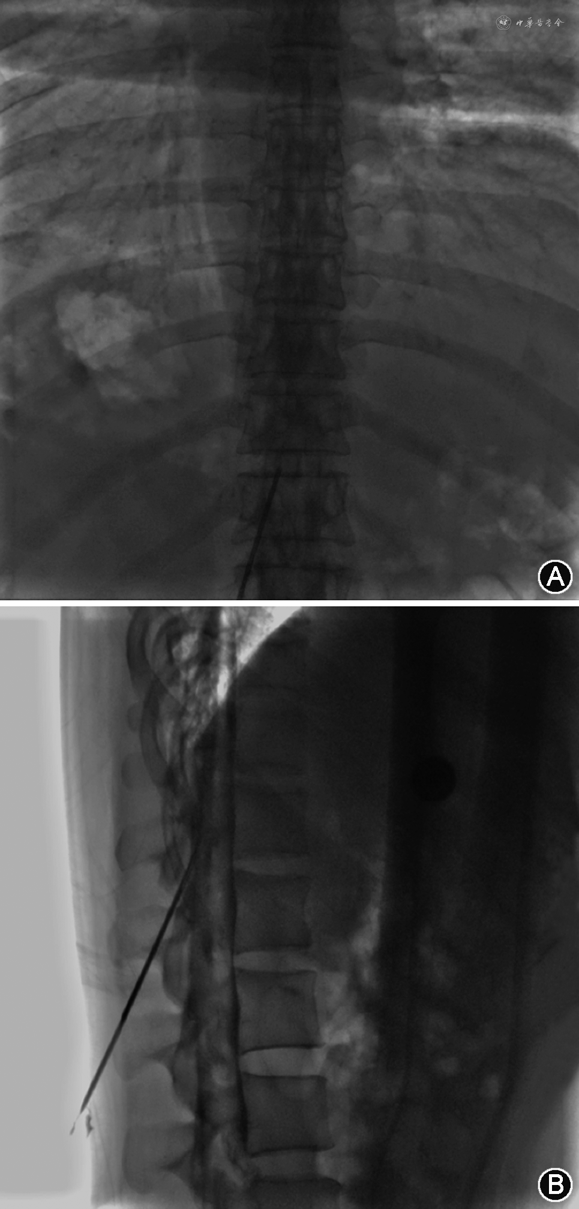

1.靶向EBP:(1)定义:靶向EBP是指根据漏口位置,以相应漏口节段为靶点进行穿刺注射的方法。术前根据影像学结果评估漏点位置,决定穿刺节段,如颈胸交界处、上胸段、下胸段等。穿刺节段越高,其硬膜外腔隙越小,穿刺风险越大,对于上胸段及颈胸交界段的穿刺建议在CT引导下谨慎穿刺[15, 16, 17]。(2)硬膜外腔穿刺:①穿刺部位选择:单发脑脊液漏漏口,选择尾侧1~2个椎体节段;多发脑脊液漏漏口,如超过6~8个节段,可选择 2个节段穿刺,头侧穿刺点可选择漏口区域。②穿刺操作方法:患者采取俯卧位,胸腹部垫薄枕,常规消毒,铺无菌巾,建议采用后正中入路穿刺,对于硬膜外腔靶向自体血分布最为有利。首先定位上下棘突的中点,局部逐层浸润麻醉后进行穿刺,依次突破皮肤、浅筋膜、深筋膜、棘上韧带、棘间韧带、椎板间隙、黄韧带,到达硬膜外腔。应避免空气阻力测试,采用结合生理盐水阻力消失法和硬膜外腔造影技术确认穿刺进入硬膜外腔。(3)硬膜外腔造影:硬膜外腔造影可帮助判断是否进入硬膜外腔及直观评估硬膜外腔结构,避免椎旁自体血无效分布。取1 ml造影剂(碘剂与生理盐水1∶1稀释),缓慢经穿刺针推注。影像下确认造影剂沿硬膜外腔分布(沿椎管位置上下扩散,无明显局部聚集,5 min后再次拍摄图像,造影剂仍显影清楚),见图1。(4)硬膜外腔置管:如造影提示无法到达靶向漏口位置,除更换穿刺节段外,可行硬膜外腔置管,但应注意避免暴力置管损伤粘连结构导致新发脑脊液漏。(5)硬膜外腔自体血靶向注射:无菌条件下将预留的自体血混合造影剂(自体血与造影剂比例为4∶1)进行靶向注射,或单纯自体血注射做造影剂替换分布(自体血注射后,漏口部位造影剂消散)。单侧脑脊液漏切勿对侧封堵,以免漏侧硬膜外腔闭塞。腹侧脑脊液漏,务必侧位X线确认分布[6]。每个穿刺点可注射10~20 ml自体血,注意观察患者有无背痛、头痛、恶心及心率、血压变化。硬膜外腔自体血注射时一定要缓慢,避免瞬间压力过大,造成颅压、血压、心率的波动,瞬时压力过大也容易使封堵液沿漏口进入蛛网膜下腔(图2)。